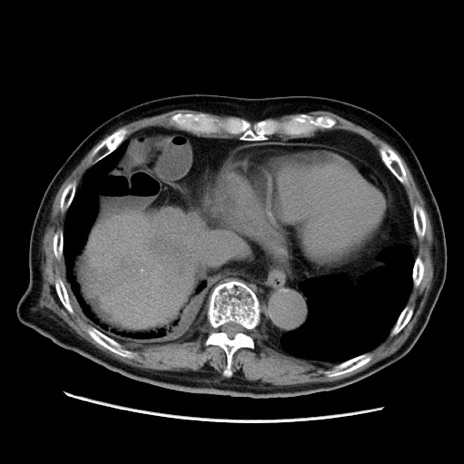

症例21(横断像)

【症例】70歳代男性

【主訴】腹痛

【現病歴】肝硬変・肝細胞癌にてかかりつけの方。約9時間前に食後より腹痛出現。症状が徐々に増悪し、嘔吐出現したため来院。

【既往歴】肝硬変、肝細胞癌(RFA、TACE後)

【身体所見】意識清明、表情苦悶様、BT 36℃、BP 129/78mmHg、P 88bpm、SpO2 97%(RA)、右上腹部から心窩部にかけて圧痛あり、反跳痛なし、筋性防御あり。

【データ】WBC 5800、CRP 0.16